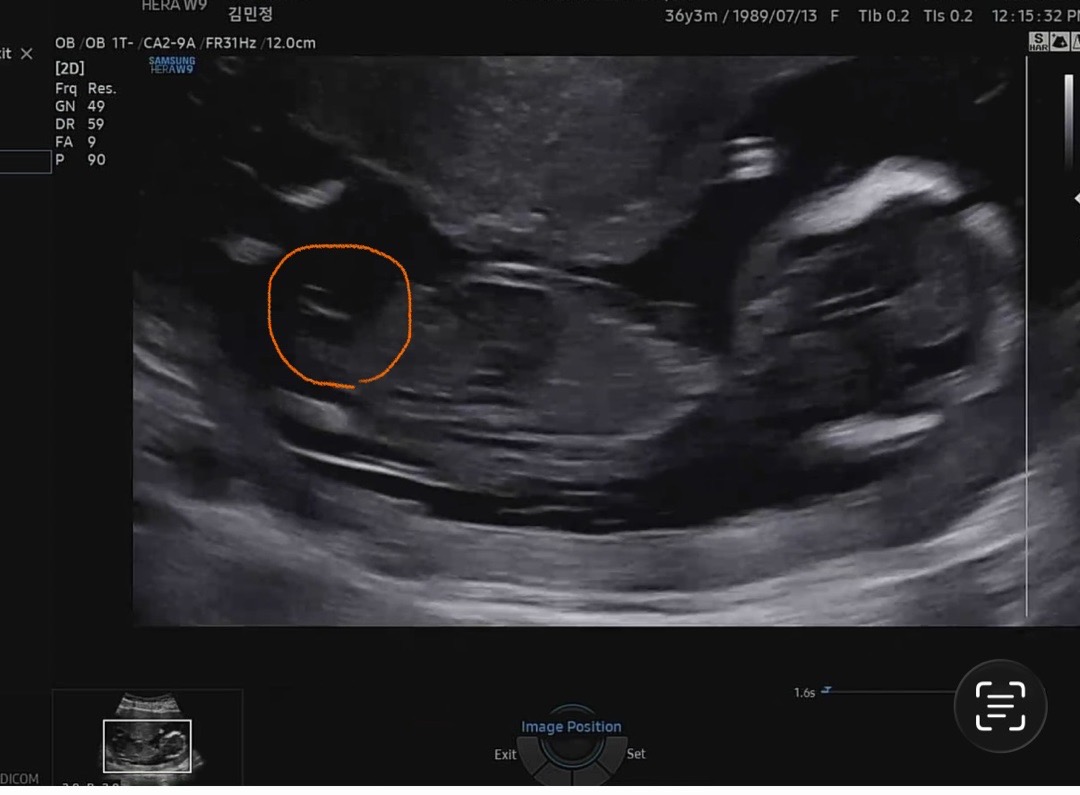

아들둘맘....13주 성별 봐주세요

딸 ㅠㅠㅠ 갖고 싶어요 제 눈엔 딸인데 ㅠㅠㅠ (딸이라고 믿고 싶을지도..) 댓글에 사진 하나 더 첨부 할게요